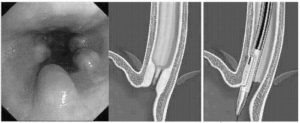

Этот способ достаточно болезненный, требует терпения от пациента, не гарантирует полного излечения. Назначается обычно в тех случаях, когда стриктуры очень небольшие, короткие, или же когда операции противопоказаны по тем или иным причинам.3. Внутренняя оптическая (визуальная) уретротомия – эндоскопическим методом рассекают стриктуры внутри уретры.

Также не всегда эффективна, иногда требует после себя бужирование.4. Стент – установка в уретру специальной пружинки, расширяющей уретру и облегчающей мочеиспускание; может давать осложнения, такие, как инфекция, пролежни, миграция стента и некоторые другие.5. Пластика уретры – восстановление канала уретры из других тканей самого пациента.